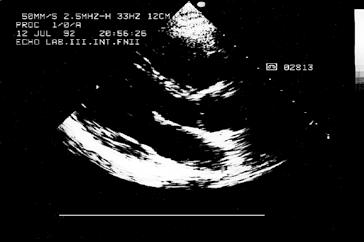

Kromě nakladatelství a výtvarníka se o definitivní podobu třetího dílu učebnice zasloužili mnozí odborníci. Za poskytnutí rtg snímků jsem již od vzniku 1. vydání 3. dílu učebnice vděčný Radiodiagnostické klinice 1. LF UK a paní doc. MUDr. Běle Drugové, DrSc., z radiodiagnostického oddělení Nemocnice Na Homolce. Za vynikající mikrofotografie z vývoje oka děkuji panu prof. MUDr. Františku Vrabcovi, DrSc., který mi je poskytl pro tuto knihu. Panu prof. MUDr. Oldřichu Eliškovi, DrSc., a paní doc. MUDr. Miloslavě Eliškové, CSc., děkuji za poskytnutí podkladů z jejich studií pro vytvoření obrazů mízního odtoku ze srdce. Panu doc. MUDr. Jaromíru Hradcovi, CSc., ze III. interní kliniky 1. LF UK děkuji za poskytnutí echokardiografických obrazů srdce. Upřímně děkuji též oběma spolupracovníkům, panu prof. MUDr. Rastislavu Drugovi, DrSc., a panu prof. MUDr. Miloši Grimovi, DrSc., za porozumění a sympatickou spolupráci na tomto vydání knihy. Studentům, učitelům anatomie i lékařům přeji, aby jim kniha sloužila jako užitečný průvodce a pomocník při studiu tohoto náročného oboru.